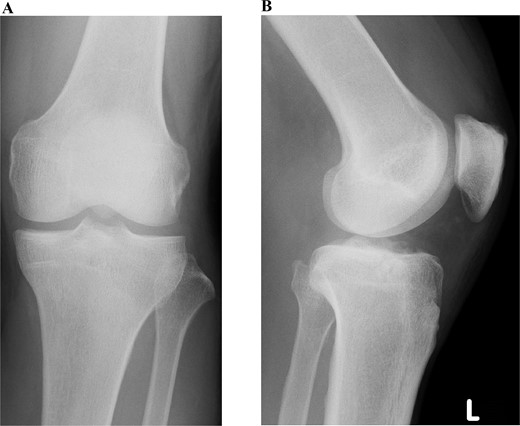

A 49-year-old male patient fell while playing soccer and visited our hospital with severe pain and swelling in his left knee. A lateral-view plain radiograph showed articular depression of the tibial plateau (Fig. 1). Three-dimensional reconstructed computed tomography (CT) scan revealed a 5-mm depression of the medial articular surface and a split in the medial plateau (Fig. 2). The fracture was classified as AO/OTA 41B3.2 and Schatzker type 2 [6, 7]. MRI scan showed a medial femoral cartilage injury that appeared as a kissing lesion opposite the tibial fracture. The length and width of the cartilage defect on the femoral condyle were 18 mm and 20 mm, respectively (Fig. 3). A part of the peripheral cartilage around the defect was suspected to be delaminated, and the defect was estimated to exceed 4 cm2.

Preoperative plain radiographic images of the left knee. Articular depression of the tibia is shown on a lateral-view radiograph.